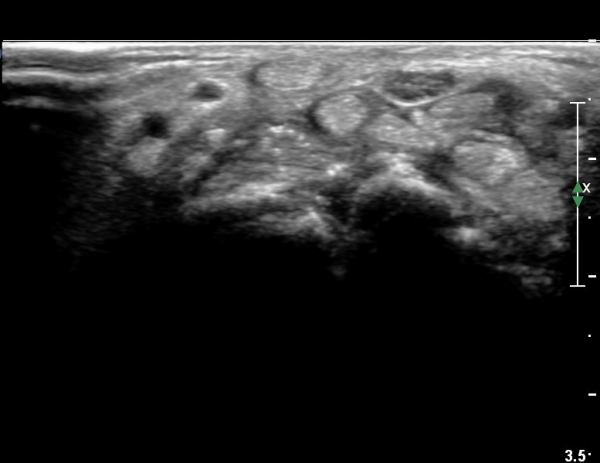

¼ö±Ù°ü Á¾´Ü¸é°Ë»ç¿¡¼ ±¼°î°Ç ½ÉºÎ¿¡ ¼®È¸È¼º À½¿µÀÌ Á¸ÀçÇϰí Àü¹ÝÀûÀÎ ¼öÁö ±¼°î°ÇÀÇ ºñÈÄ, Á¤Á߽ŰæÀÇ ºÎÁ¾°ú

ÈûÁÙ ¹× Á¤Á߽ŰæÀÇ Ç¥ÃþÀ¸·Î ÀüÀ§°¡ °üÂûµÈ´Ù, (»çÁø 5, 6,). ÆÄ¿öµµÇ÷¯°Ë»ç¿¡¼ Ç÷·ùÁõ°¡°¡ °üÂûµÊ´Ù(»çÁø 6).